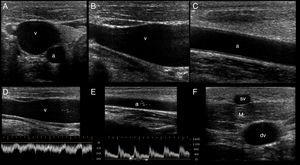

Depth, gain and focal zones are the most important machine parameters that practitioners always need to optimize to carry out the best possible evaluation on the vessels. Preferably, tissue harmonic imaging must be switched off, especially for further needle recognition8 (see below) (Fig. 2).

Proper basic technical parameters to optimize the image for vascular cannulation. The focus zones, which are two in this case (arrows), are positioned in superficial tissues and in line with the vessel, so as to improve resolution in these regions, thus best delineating the vessel and its surrounding structures and further recognizing the needle and its insertion in the vessel. Depth must be adjusted involving the vessel posterior wall and the structures behind it, in order to select or discard a vessel for cannulation (e.g. artery over vein overlapping) and to readily detect an inadvertent puncture of the vessel posterior wall. Proper gain adjustment (general gains and near-far field gains using the time-gain compensation controls) are essential: too high gains can mask the echogenicity of the needle between the tissues, while too low gains may obscure the echogenicity of the needle as well as the vessel. Finally, using fundamental imaging is advocated, since tissue harmonic imaging is associated with poorer needle recognition.

US mapping before cannulation. (A) Patent vein, confirmed by full compressibility (arrows); (B) thrombosed common femoral vein, clearly seen enlarged and occupied by a large thrombus (t); a: common femoral artery. (C) vein valve; v: vein; (D) optimal vein diameter for central venous cannulation; (E) optimal vein diameter and distance from skin to vein for peripheral vein cannulation; (F) artery with two calcified atheromatous plaques (calipers).

First, the patency of the vein must be demonstrated along its course applying anteroposterior compression forces in short axis views. Normally, a patent vein is fully compressible (Fig. 4A). A vein having a thrombus is not compressible or is partial compressible and thus it is discarded for cannulation (Fig. 4B).

Secondly, vein valves (Fig. 4C) must also be avoided when selecting the site of cannulation, since this may make the catheter passage difficult as well as damaging the vessel and predisposing it to thrombosis.2,7

Thirdly, the veins must have a normal diameter to be successfully cannulated. For central veins, an optimal anteroposterior diameter≥7mm is recommended2; for peripheral veins≥4mm4 (Fig. 4D and E).

In peripheral vein cannulation, the selected vein must be superficial by definition, thus avoiding any possibility to injure an artery. An optimal distance from skin to the vessel <16mm is important to avoid the premature dislodgement of the catheter3,4 (Fig. 4E). In other cases, a longer catheter (e.g. 8–20cm, “midline catheters”) can be used if the vein is more deeply located but still has an optimal dimension.9 The latter is commonly seen in the basilic vein of the arms. Furthermore, a peripherally inserted central catheter (PICC) can be inserted in these veins.7

When selecting arteries, permeability is assessed observing the normal luminal anechoic content as well as the vessel pulsatility in real time. Color and spectral Doppler can be used but are seldom required for this purpose. It is important that the arterial wall does not contain an atheromatous plaque in the future site of puncture, since this may lead to plaque accident and a thromboembolic complication (Fig. 4F). As opposed to veins, there is no optimal recommended artery diameter for cannulation.